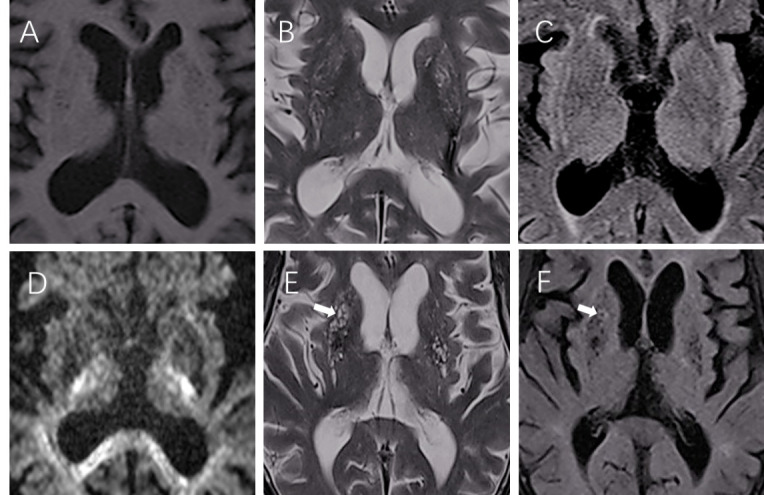

Method: A matched case-control study was conducted in Xiamen, China. A total of 184 IS patients (cancer vs control=1:1) were recruited. The severity of BG-EPVS was graded using high-resolution MRI. Patients' gender, age, clinical risk factors, other imaging changes and laboratory findings information at admission were collected. Logistic regression models were constructed and subgroup analysis by cancer treatment.

Abstract Image